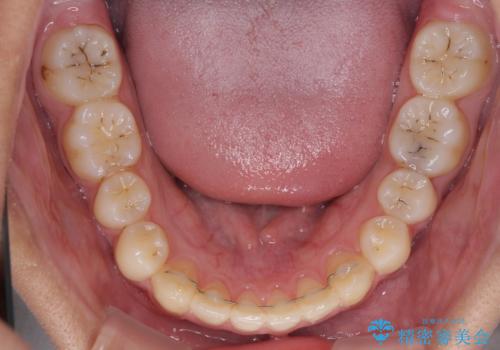

- 前歯のデコボコと隙間を気にして来院された高校生の患者様です。

下顎前歯が上顎前歯を突き上げるような咬み合わせとなっており、その影響で上顎正中に隙間ができている状態でした。

叢生の程度は軽度であり、本人もしっかりと使用する自信があるとのことだったので、インビザラインによる矯正治療を行うこととしました。

突き上げによる隙間を予防する為に、深い咬み合わせを改善するような治療計画としました。咬み合わせを改善させることはできましたが、隙間は後戻りしやすいので、通常の下顎前歯のみではなく、上顎前歯2本もワイヤーで保定を行いました。

高校生ということで、非常に短期間で治療を終えることができました。